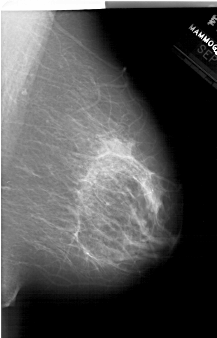

A_1514_1.LEFT_CC

LEFT_CC LINES 6871 PIXELS_PER_LINE 4381 BITS_PER_PIXEL 12 RESOLUTION 43.5 OVERLAY